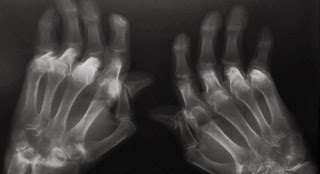

La artritis reumatoide es una enfermedad sistémica autoinmune, crónica, que afecta principalmente a las articulaciones y a las mujeres. Además, esta patología suele aparecer en la edad media de la vida y su prevalencia en la población es cercana al 0,5%.

"Aunque su causa es desconocida, se han identificado factores medioambientales y genéticos involucrados en su desarrollo. La enfermedad representa un gran costo socioeconómico y un impacto adverso en la calidad de vida de los pacientes. A pesar del gran desarrollo alcanzado en los últimos años en su tratamiento, es necesario el descubrimiento de nuevos fármacos más eficaces y específicos", ha zanjado el experto.